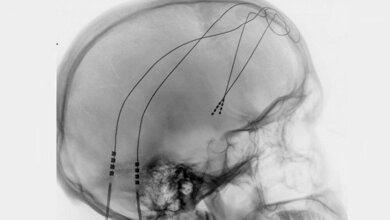

Die acht Probanden litten zwischen drei und elf Jahre durchgehend an einer schwersten Depression, bei der weder medikamentöse oder psychotherapeutische Behandlungen noch Stimulationsverfahren wie die Elektrokrampftherapie Besserung brachten. Die Ärzte implantierten hauchdünne Elektroden und stimulierten einen Hirnbereich, der an der Wahrnehmung von Freude beteiligt und damit auch für Motivation und Lebensqualität von Bedeutung ist. Die Wirkung der Therapie bewerteten die Ärzte monatlich mit Hilfe der etablierten Montgomery-Asberg Rating Scale (MARDS). Bereits im ersten Monat fiel der MARDS-Wert im Durchschnitt von 30 Punkten auf 12 Punkte und sank bis zum Ende der Studie sogar noch weiter leicht ab. Den MARDS-Wert von 10 Punkten, ab dem eine Depression diagnostiziert wird, unterschritten vier Personen.

Manche Patienten litten kurzzeitig unter verschwommenem Sehen oder unter Doppelbildern. „Die Nebeneffekte konnten wir durch eine verminderte Stimulationsstärke beheben, ohne dass der antidepressive Effekt der Therapie nachgelassen hätte“, sagt Prof. Dr. Volker A. Coenen, Leiter der Abteilung Stereotaktische und Funktionelle Neurochirurgie an der Klinik für Neurochirurgie des Universitätsklinikums Freiburg. Bei keinem Patienten waren Persönlichkeitsveränderungen, Denkstörungen oder andere Nebenwirkungen zu beobachten.